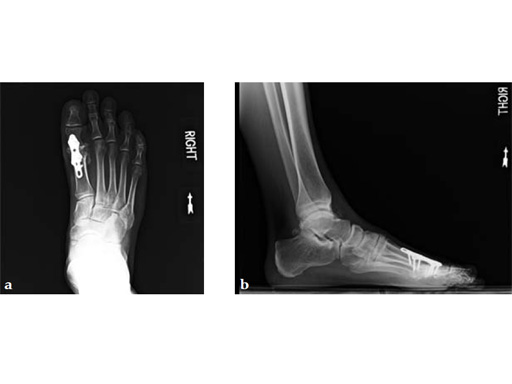

Case 3: First TMT fusion plate

A 48-year-old woman, with hallus valgus and hypermobile medial column, also resulting in pes plano abductovalgus (flatfoot).

Case provided by Andrew Sands, New York, New York, USA

Surgery consisted of first TMT and intertarsal corrective osteotomy plus fusion with movement of the first MT lateral and plantar. This corrects the hallus valgus as well as the PPAV (and stabilizes the medial column).